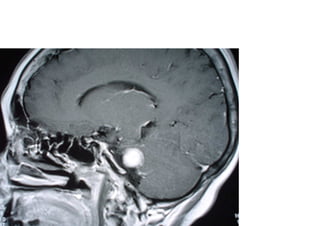

Vascular

Hemorragica

Isquemica

Neoplasica